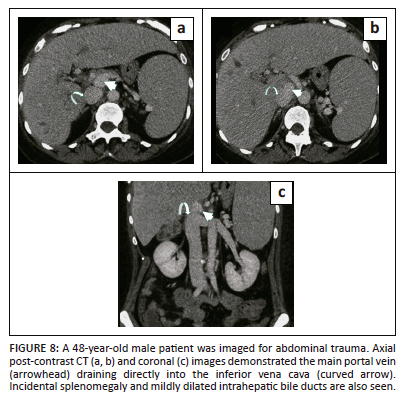

Extrahepatic portocaval shunt or Abernethy malformation

The portal vein is formed cranially from a segment of the prehepatic right vitelline vein, the intervitelline anastomosis, and caudally from the left vitelline vein around the fifth week of life.19 The right vitelline vein thus serves as a common conduit during the development of both the IVC and the portal vein. The process of formation of hepatic tissue results in disruption of intervitelline vein anastomosis disconnecting the cranial and caudal segments of the portal vein. Eventually, the cranial segment of the portal vein disappears. Hence, there is no direct communication between the portal vein and the IVC.19 These extrahepatic portocaval shunts may result either from excessive involution of the vitelline vein or failure of the vitelline vein to establish an anastomosis with the hepatic sinusoids or hepatic veins.9,27

Abernethy malformations are of two types. Type 1 is more common in females and is characterised by complete shunting of portal blood into the IVC and an absent portal vein (Figure 8). It is associated with congenital cardiac, gastrointestinal (e.g., biliary atresia) and genitourinary anomalies.9,19 Type 2 is more often seen in males as an isolated abnormality with partial end-to side anastomosis between an intact portal vein and the IVC resulting in shunting of blood. The presence or absence of the portal vein is an important imaging finding because it helps to distinguish between the two types. The Abernethy malformation is associated with focal nodular hyperplasia and hepatocellular carcinoma (HCC).7,9 Type I is managed with a liver transplant. The Type II shunt may require occlusion of the shunt if the patient develops hepatic encephalopathy or bleeding varices. It can be managed surgically or percutaneously using balloons or coils.19